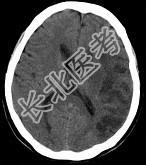

- 单项选择题男,62岁, 8小时前患者突发右侧肢体瘫痪1天,构音不清, CT检查如图,最可能的诊断是 ( )

A、脑梗死

B、星性胶质瘤

C、脑脓肿

D、少突胶质细胞瘤

E、血管母细胞瘤